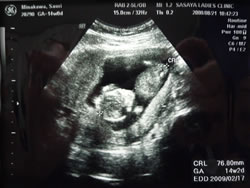

9月4日:妊婦検診・・・オナカの赤ちゃん(96mm)

約1ケ月で 倍の大きさになった ベビちゃん。

オナカの赤ちゃん♪ |